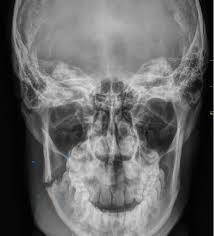

Sebastián Gómez, de 21 años, fue brutalmente agredido durante la madrugada del sábado 14 de febrero a la salida del boliche El Bosque, ubicado sobre la avenida Goycoechea. El joven sufrió una fractura de mandíbula y deberá ser sometido a una cirugía.

Sebastián fue atendido en el Hospital Cura Brochero y luego derivado al Hospital de Urgencias, donde confirmaron la necesidad de una intervención quirúrgica con placas de titanio. El costo supera los dos millones de pesos.